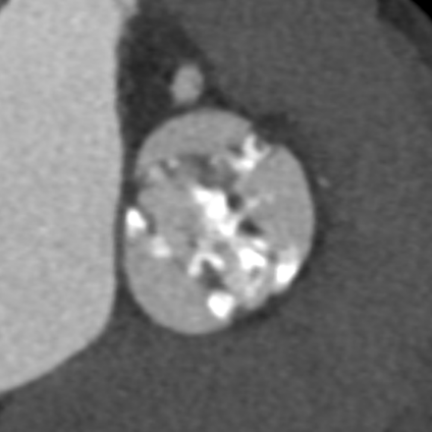

置入纽脉医疗29mm球囊扩张式PrizValve

最终造影显示人工瓣膜位置理想,无明显中心或瓣周反流,升主动脉、主动脉弓及降主动脉均未见明显主动脉损伤征象。

术后主动脉根部造影